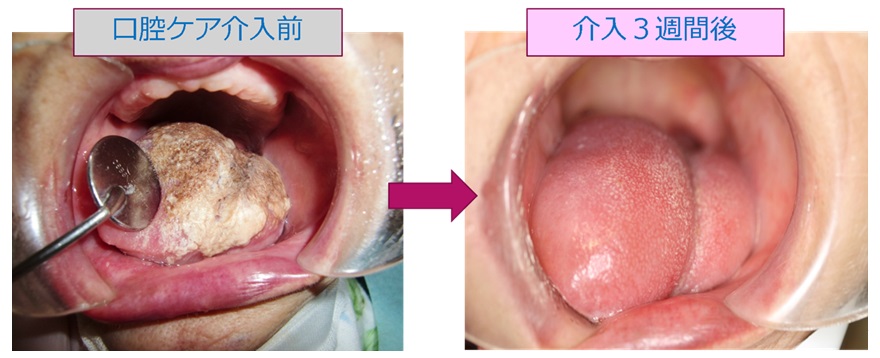

治療症例

周術期口腔ケア

周術期口腔ケアは、手術の前後に行う口腔内のケアで、手術の成功と術後の回復を支援する重要な役割を果たします。手術前に口腔内の清潔を保つことで、感染リスクを減少させ、合併症の予防に繋がります。

また、術後の口腔ケアは、治癒を促進し、痛みや腫れを軽減する効果があります。

具体的なケア内容には、専門的な歯科クリーニング、歯石除去、歯周病の治療、虫歯の処置が含まれます。

また、患者さんご自身による正しい歯磨き方法の指導や、うがい薬の使用も推奨されます。